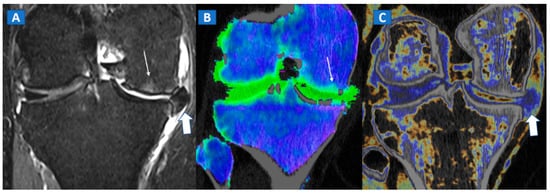

The diagnosis of osteonecrosis, defined as the ischemic death of bone, is based on the presence of a double line sign, BME, and subchondral fractures at MRI. With standard high-resolution CT images available (Figure 5), DECT can been used to identify BME and associated imaging findings, as well as to reliably diagnose AVN of the femoral head [9]. Importantly, DECT images can reliably identify subchondral fractures and cortical bone involvement, which are key in the prognosis and management of AVN of the femoral head (Figure 5). Thanks to high resolution images, DECT could be used for staging AVN, depicting for example cystic and sclerotic radiographic changes in early phases, or BME around sub-chondral collapsed areas. CT is also a highly reliable imaging tool in evaluating articular narrowing and calcific loose bodies.

Figure 5.

A 58-year-old female with AVN of the right femoral head. On the coronal STIR MRI image (A), a hypointense serpiginous subchondral line, evident as a double line sign (arrow), is associated with diffuse BME involving the femoral neck and trochanteric region. On the corresponding T1-weighted image (B), hypointense BME seems to spare the medial aspect of the femoral head. On the DECT coronal 3D image (C), a flattened subchondral edematous area is depicted, with sclerosis-related artifacts hindering clear imaging of any BME of the head (thick arrow), although BME is apparent on the femoral neck. On the corresponding 1 mm coronal CT image with a soft-tissue window (D), it is possible to depict an increased density corresponding to the BME distribution (thick arrow), and a subtle subchondral hypodense line, which would be consistent with the diagnosis of a subchondral fracture (thin arrow). R = right.